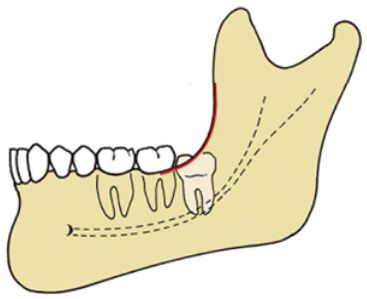

9.圖中所顯示的阻生齒,是屬於 Pell and Gregory 的那一種分類?

(A)class 2 B (B)class 2 C (C)class 3 B (D)class 3 C